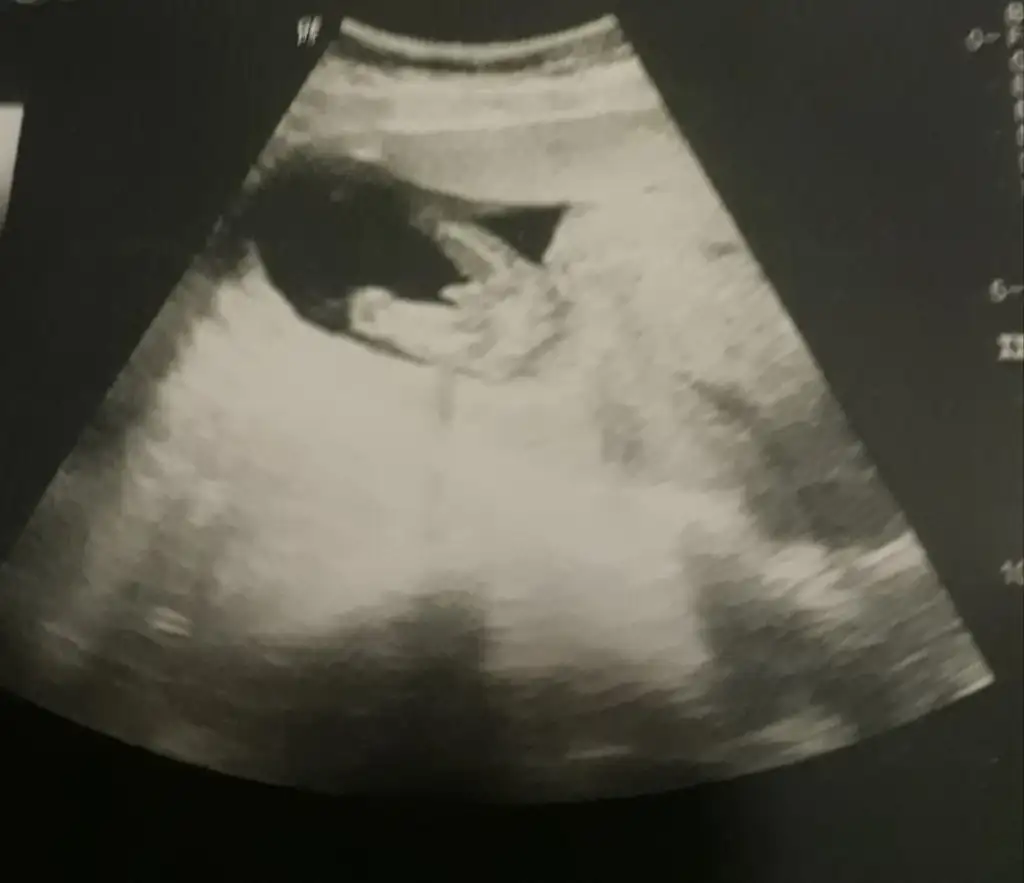

dr soylemeden siz gorun genital nub teorisi ( bebegin cinsiyeti)

Bu gördüğüm nub ise hafif dik görünüyor 😬

Aynen hayırlı saglıklı gönlündeki olur inşallah eminde olamadım tam dik değil hafif dik gibi 😬